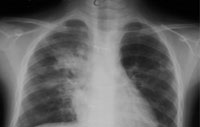

X线胸片1: 入院时(病程2个月时)胸片(右肺门外及左下肺心缘旁可见片影,左上肺纹理乱,右肺门著明,心影丰满) X线胸片

2:入院第7天(病程67天)胸片:右肺门增浓,边缘模糊,下肺纹理模糊,左肺纹理粗乱,下肺纹理模糊

任甄华 主治医师(放射科):X线胸片对于提示肺栓塞有重要参考价值,单纯肺栓塞胸片可能有五种表现:(1)缺血性改变:局部血管纹理减少,即Westermark征;(2)肺血管大小的改变;(3)心脏变化;(4)肺体积缩小;(5)胸膜渗出。值得强调的是,感染性心内膜炎引起的肺栓塞影像学改变与其他病因引起者不同,典型表现为散在、双侧的外周结节与不同程度的肺空洞性损害,损害呈圆形或楔形,多发生在下肺的外侧部分。本病例就体现了这一特点(见附图),这可能与栓子较小且携带病原菌,造成栓塞部位的继发感染有关。

但必须指出,肺栓塞的X线胸片表现多种多样,呈典型锥形改变的非常少见,部分肺栓塞的胸片可看不见任何异常表现。相当一部分胸片呈肺浸润表现,与肺炎相似。可从以下两点加以区别:①肺部一侧病变吸收,而另一侧出现新阴影的多发病变;②片影吸收呈“溶化征”,而肺炎吸收中片影出现密度不均现象,由此可见,在诊断中胸片的动态观察更为重要。有以上表现者应高度怀疑肺栓塞,再结合患儿是否存在高危因素,临床可做出正确诊断。切勿仅凭胸片轻易排除肺栓塞。本例患儿存在感染性心内膜炎、三尖瓣赘生物的基础病变,2个月病程中肺部阴影变化了3次,每次均为原有病灶吸收,在不同部位又出现了新的浸润影,结合临床表现,肺栓塞可确诊。